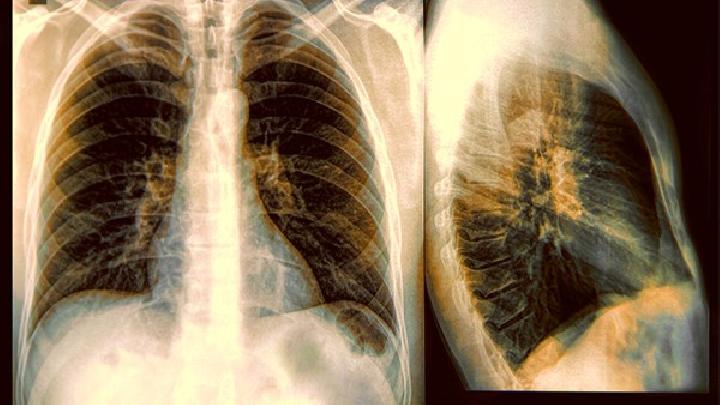

肺疟疾是疟原虫感染后对身体的损害发病时会咳嗽胸痛,严重时还会出现肺水肿或呼吸衰竭。肺也是一个重要的器官,是我们的呼吸系统。如果你患有肺疟疾,你应该立即治疗。不要等到病情严重恶化后才开始注意。那时,治疗会非常麻烦和危险,患者的身体损伤会大得多!